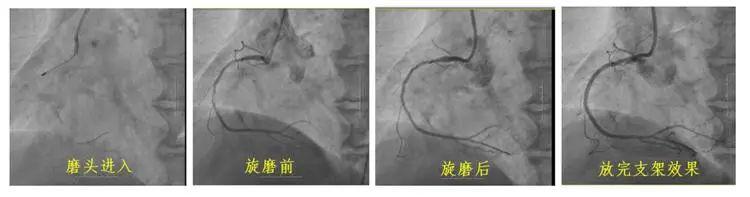

冠狀動脈鈣化因其致密堅硬的病變特征,長期制約著心血管介入治療效果。長春國文醫(yī)院心血管內(nèi)科團隊引入冠狀動脈旋磨技術(shù),在血管內(nèi)超聲(IVUS)實時導(dǎo)航下,以每分鐘15萬轉(zhuǎn)旋磨技術(shù)精準(zhǔn)粉碎鈣化斑塊,成功為一名右冠狀動脈100%閉塞的73歲患者實現(xiàn)血管再通。該技術(shù)的成熟應(yīng)用,標(biāo)志著醫(yī)院在旋磨技術(shù)處理復(fù)雜鈣化病變的臨床可靠性,為更多心血管疾病患者帶來康復(fù)希望。

冠狀動脈旋磨術(shù)作為一項先進且高難度的冠脈介入治療技術(shù),在處理冠狀動脈嚴(yán)重鈣化病變方面具有獨特優(yōu)勢。其基于精確的“差異切割”原理,通過高速旋轉(zhuǎn)的旋磨頭,精準(zhǔn)地對鈣化或纖維化的動脈硬化斑塊進行祛除,同時巧妙避開有彈性的血管組織及正常冠狀動脈,從而極大地降低對血管中膜的損傷風(fēng)險。該技術(shù)具有精確性高、安全性強、效果持久以及適用范圍廣等顯著特點,能夠有效減輕冠脈狹窄程度,顯著改善心肌供血狀況,為冠心病等心血管疾病的治療開辟新路徑。